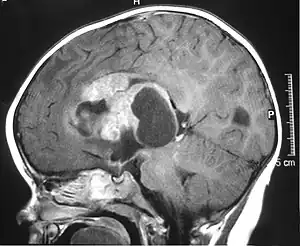

| MRI of an AT/RT | |

The initial diagnosis of a tumor is made with a radiographic study (MRI[20] or CT-). If CT was performed first, an MRI is usually performed as the images are often more detailed and may reveal previously undetected metastatic tumors in other locations of the brain. In addition, an MRI of the spine is usually performed. The AT/RT tumor often spreads to the spine. AT/RT is difficult to diagnose only from radiographic study; usually, a pathologist must perform a cytological or genetic analysis.

Appearance on radiologic exam

AT/RTs can occur at any sites within the CNS; however, about 60% are located in the posterior fossa or cerebellar area. The ASCO study showed 52% posterior fossa; 39% sPNET; 5% pineal; 2% spinal, and 2% multifocal.[1]

The tumors' appearance on CT and MRI are not specific, tending towards large size, calcifications, necrosis (tissue death), and hemorrhage (bleeding). Radiological studies alone cannot identify AT/RT; a pathologist almost always has to evaluate a brain tissue sample.

The increased cellularity of the tumor may make the appearance on an uncontrasted CT to have increased attenuation. Solid parts of the tumor often enhance with contrast MRI finding on T1 and T2 weighted images are variable. Precontrast T2 weighted images may show an isosignal or slightly hypersignal. Solid components of the tumor may enhance with contrast, but not always. MRI studies appear to be more able to pick up metastatic foci in other intracranial locations, as well as intraspinal locations.

Preoperative and follow-up studies are needed to detect metastatic disease.